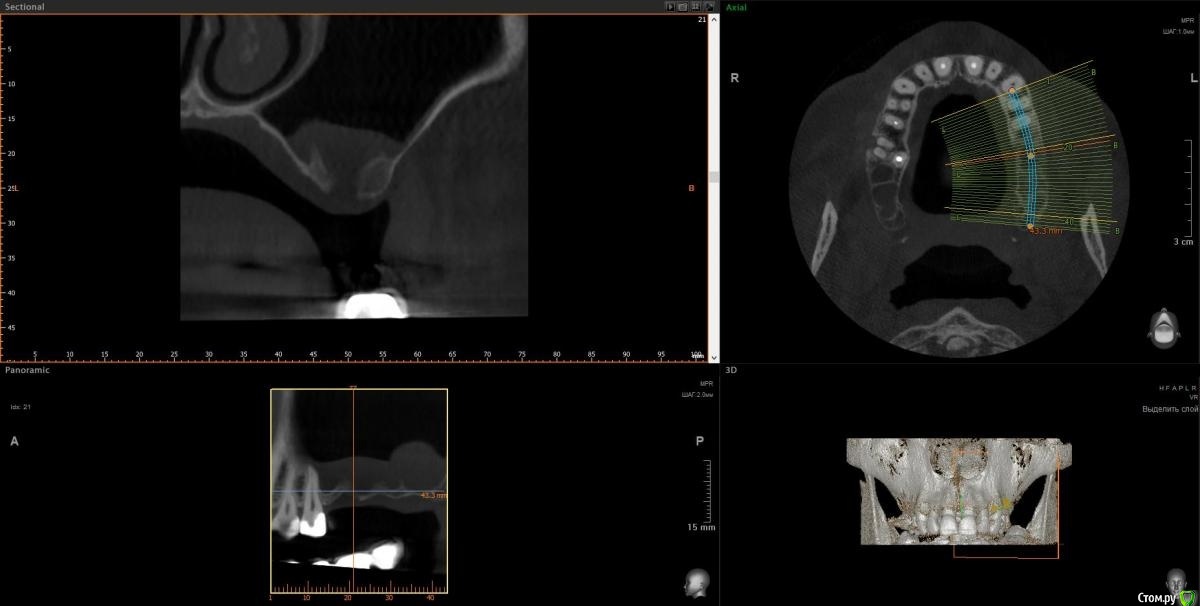

Doctor Vlad Опубликовано 24 сентября, 2020 Автор Поделиться Опубликовано 24 сентября, 2020 27 удалил месяцев 3 назад, отмыл пазуху, зашил все заплаткой сст. сообщение закрылось. снимок кт свежий. хочу 2 импланта туда поставить. дефект костный дна синуса ламиной закрыть на винтах. все равно слой своей кости не велик, стружка понадобится. какие будут мнения? Ссылка на комментарий

Doctor Vlad Опубликовано 24 сентября, 2020 Автор Поделиться Опубликовано 24 сентября, 2020 (изменено) Самое главное забыл. кт свежее! и снимок на этапе зашивания соустья удаления 27 Изменено 24 сентября, 2020 пользователем Doctor Vlad Ссылка на комментарий

kriokov Опубликовано 24 сентября, 2020 Поделиться Опубликовано 24 сентября, 2020 какие будут мнения? клкт свежее сделайте, может там без лишней оротьбы обойдется-- синус и два болта, Ссылка на комментарий